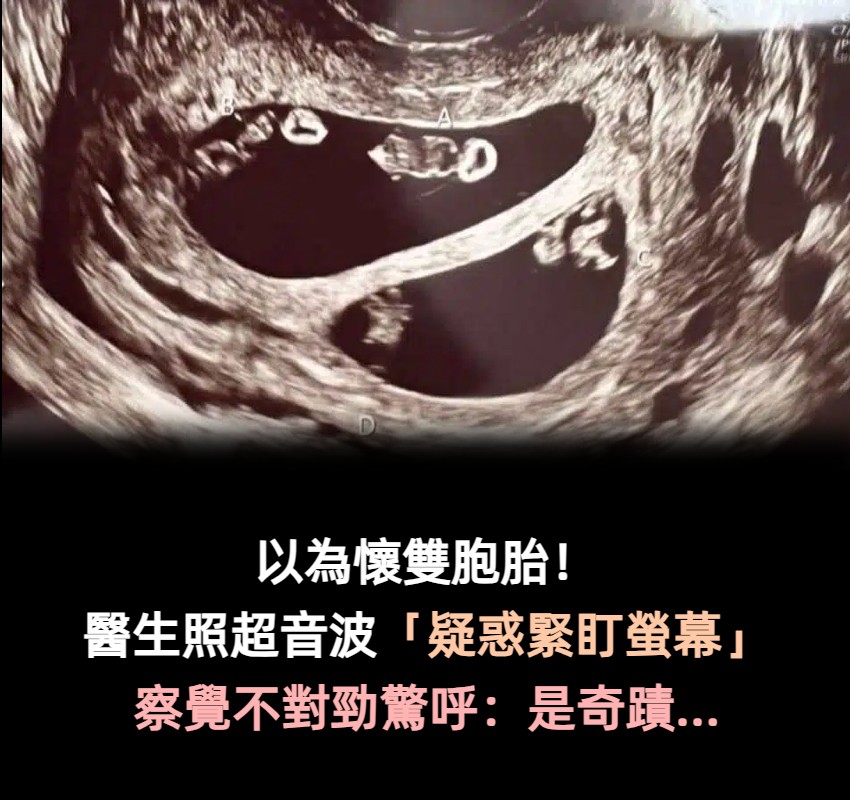

以為是懷雙胞胎!醫生幫她照超音波「疑惑緊盯螢幕」 走出房間驚呼「千萬分之1的奇蹟」全場嚇傻

(圖片來源:People)

醫生在照超音波時發現驚人景象,艾希莉本來以為自己是懷著一對雙胞胎寶寶,沒想到醫生疑惑的看著螢幕好久,又走出房間請同事一起來觀察,最後才確定她竟然懷上了2對同卵雙胞胎,分別為2男2女,而醫師也解釋這狀況在醫學上發生機率僅7千萬分之一,根本就像是中了一張大樂透般不可思議!

(圖片來源:People)